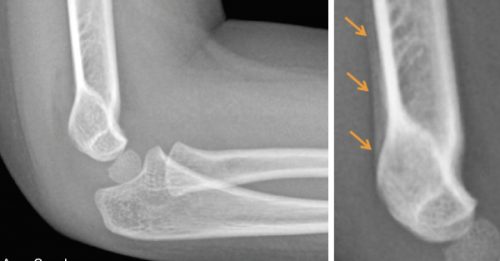

• How to Avoid Missing a Pediatric Elbow Fracture

How to Avoid Missing a Pediatric Elbow Fracture